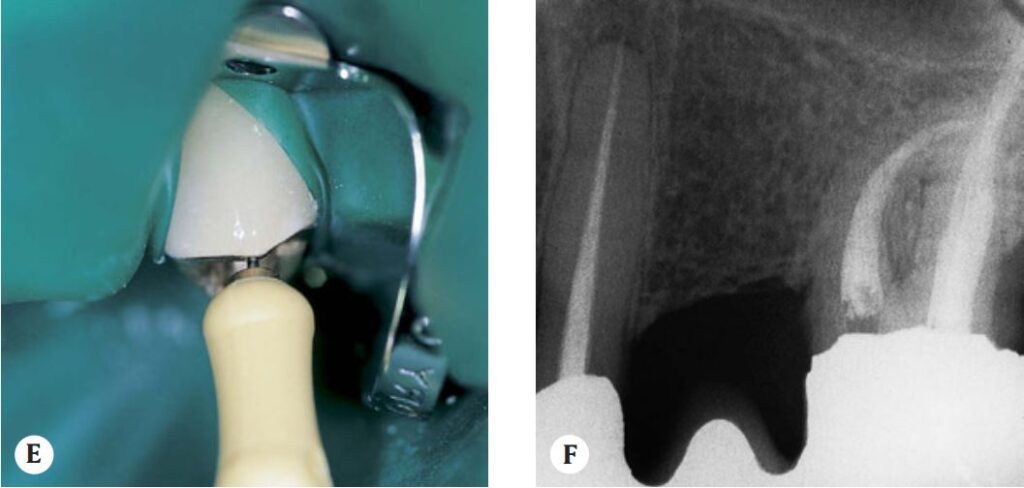

Ca lâm sàng

Sau khi sửa soạn phần thân răng, các trâm nhỏ hơn sẽ đi xuống sâu hơn vào ống tủy cho đến khi các trâm nhỏ nhất đạt đến chóp chân răng. Tuy nhiên, trong mọi trường hợp, trâm K số 15 phải được sử dụng để xác định độ thông suốt của toàn bộ chiều dài ống tủy.

Sau khi mở rộng phần ống tủy thân răng, chiều dài làm việc được xác định bằng chụp X quang với trâm số 15. Độ lệch hơn 2mm so với độ sâu làm việc đã thiết lập không được hiệu chỉnh ngay lập tức mà chỉ sau khi dụng cụ ở phần ba vành và giữa của ống tủy, sử dụng phép đo X quang thứ hai.

Bắt đầu mở rộng phần thân răng bằng trâm K #35; trâm này chỉ đi xuống được một vài milimet ở phần phía trên (phần 1/3 trên) của ống tủy, sau đó được sửa soạn để mở rộng cẩn thận. Sau đó, ống tủy được bơm rửa sạch và trâm #15 được sử dụng để kiểm tra độ thông suốt của ống tủy.